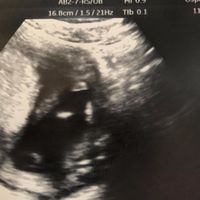

Mamme e future mamme finalmente trovò un po’ di tempo x scrivervi e dirvi ke la mia piccolina dopo l’ultima visita andata un po’ così finalmente è cresciuta, i medicinali fanno il loro effetto e devo...

Ciao ragazze. Chi come me ha la dpp a Maggio 2018? Io ultimo ciclo 26 luglio (ma ho cicli molto lunghi e irregolari). Ho utilizzato la tb quindi pensavo di aver ovulato il 22 agosto con dpp 15 maggio,...